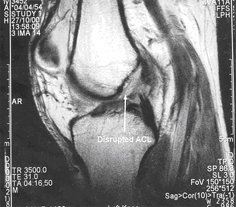

This will show all the structures in the knee and enables a reliable diagnosis to be made however, scans are very expensive and are not always available or if they are, there may be an unacceptably long wait.

B. The second image demonstrates a torn ACL.